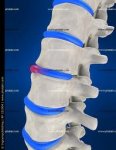

Грыжа позвоночника поясничного отдела: симптомы и лечение

Грыжа позвоночника поясничного отдела, одно из самых опасных и коварных заболеваний. Данный недуг вызывает боли в поясничном отделе, можете просто болеть нога, через некоторое время может проявляться скованность в движениях. В пояснице наблюдаются 5 позвоночников, врачи обозначают их латинской буквой L. Данные позвоночники соединены между собой межпозвоночными дисками.